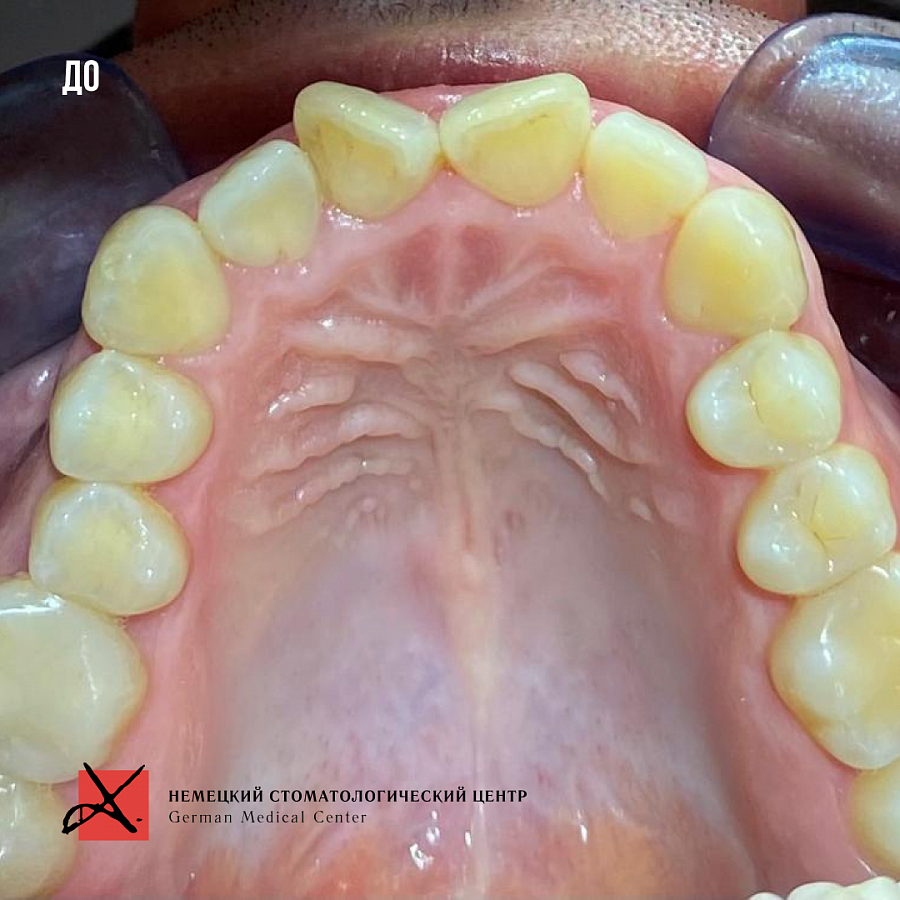

Какой диагноз поставили

- сужение верхней челюсти

- открытый прикус во фронтальном отделе

- обратный прикус в боковых отделах

- скученное положение зубов обеих челюстей